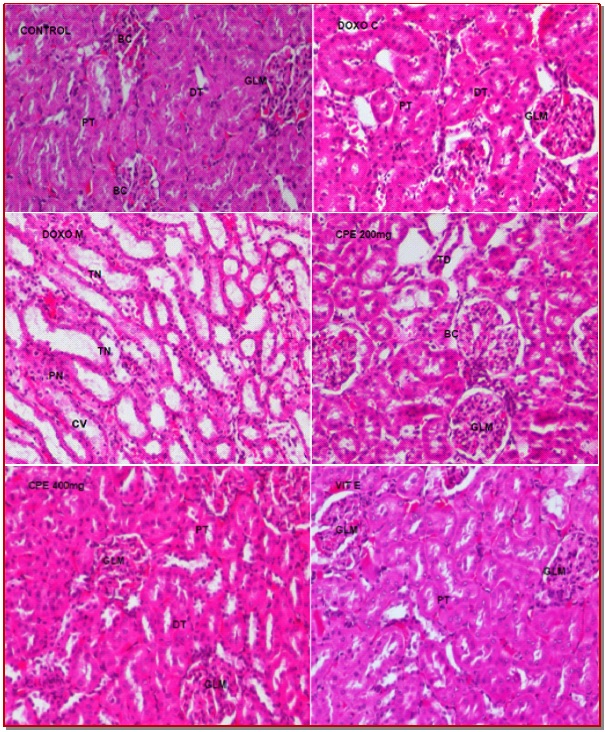

The present study was conducted to evaluate the nephroprotective effect of a medicinal herb Costus pictus against doxorubicin-induced toxicity. Rats were divided into six groups and treated with doxorubicin and ethanol extract of the C. pictus. Doxorubicin was administered intraperitoneally with a single dose (4 mg/kg) per week for three weeks. The extract (200 or 400 mg/kg) was administered orally for 4 weeks to two doxorubicin groups. Significant changes of the serum kidney markers, albumin, urea, uric acid and creatinine, and glutathione peroxidase, glutathione–S-transferase, catalase, superoxide dismutase, reduced glutathione and lipid peroxides in the kidney of doxorubicin-treated rat were observed. Histological features were also severely affected. However, biochemical and histological changes in the extract-treated rat were non-significant, showing that the herb is nephroprotective. The effects were comparable to the anti-oxidant vitamin E.